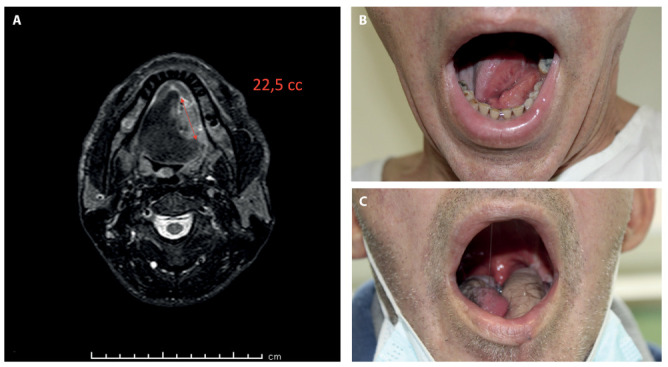

Background and aim: The radial forearm free flap (RFFf) and the antero-lateral thigh flap (ALTf) are considered the "key flaps" for oral cavity reconstruction. Nowadays, the literature lacks of an objective and standardized decision-making algorithm for the flap choice. The aim of this study is to describe a decision-making algorithm concerning the more appropriate flap, RFFf or ALTf, in the reconstruction of intra-oral soft tissues based on the volumetric analysis of the defect with a pre-operative Magnetic Resonance Imaging (MRI), updating our previous surgical experience.

Methods: We conducted a retrospective observational study including 77 patients who underwent microsurgical reconstruction with RFFf or ALTf after tumor resection of the soft tissues in the oral cavity. During follow-up, patients were evaluated using the UW-QOL questionnaire.

Results: Analyzing the scores of the UW-QOL questionnaire based on the size of the tumor on preoperative MRI we found that for tumor volume <50cc and between 50-70cc, the patients reconstructed with RFFfobtained statistically significant better scores compared to the ALTf group, while for tumor volume >70cc, the patients reconstructed with ALTf reported statistically significant better scores.

Conclusions: Pre-operative RMI-guided volumetric assessment of oral cancer plays a key role in the planning of adequate soft tissue reconstruction and can objectively help surgeons in the correct choice of the flap (RFFf vs. ALTf) for each case based on preoperative tumor size, suggesting for defects <50cc and between 50 and 70 cc a reconstruction with RFFf, while for defects >70cc a reconstruction with ALTf.